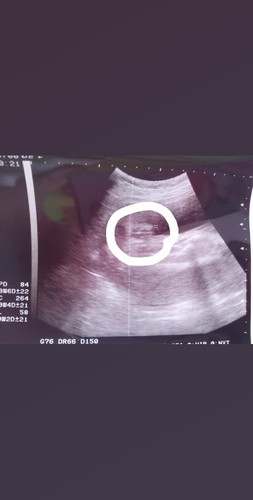

มีใครเคยเป็นไตอักเสบตอนท้องมั้งค่ะ รักษางัยยังให้หาย #ตอนนี้อยากหายมากเลยค่ะทรมานมาก ทั้งเหนื่อย เพลีย ปวดกระดูก ปวดไปทั้งตัวเลยค่ะ หัวก็ปวดทั้งวันทั้งคืน ใครมีอะไรแนะนำ แนะนำหน่อยน่ะค่ะ #ขอบคุณสำหรับคำแนะนำน้ะค่ะ